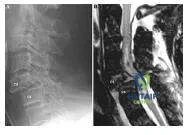

A 40-year-old woman has severe neck pain following a motor vehicle accident. Her plain lateral radiograph of the spine is shown (Slide). A sagittal magnetic resonance scan is shown (Slide). The most likely diagnosis is:

Correct Answer: Bilateral facet dislocation

Explanation:

There is significant subluxation of C 5 on C 6 on the plain radiograph. The facets of C 5 and C 6 have lost their normal relationship. This patient has a bilateral facet dislocation. There is compression and significant changes within the spinal cord. This patient should be treated with reduction and fusion.